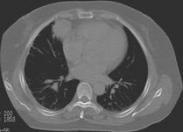

诊断一般不难。任何胸壁心脏危险区的贯穿伤,以及颈根部、上腹部、胸部、后胸壁或纵隔所贯穿伤,应提高警惕有损伤心脏的可能。在上述区域尤其是心前区有伤口,且短期内出现重度低血压、重度休克者,几乎可确立心脏损伤的诊断。

任何胸腹部外伤的病人,估计失血量与休克程度不符合,经足量输血而无迅速反应者,或初期低血压经血容量补充后迅速改善,但不久又再度出现,甚至发生心搏骤停者亦多为心包填塞所致。由于病情急、重,无须作过多检查,诊断明确即应积极手术治疗。即使心脏停跳约10分钟之内亦应积极手术抢救,可取得较理想的抢救成功率。由于条件限制,术中应回输自体胸血,术毕大剂量联合应用有效抗生素。